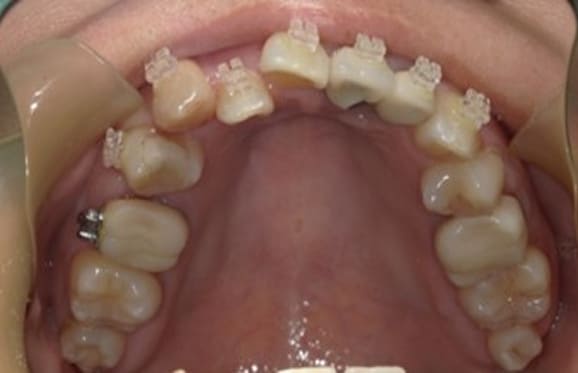

● 歯根が折れ保存不可の歯を抜歯して、そのスペースに八重歯を並べた症例

藤沢デンタルオフィスの虫歯や破折で抜歯後の部分矯正